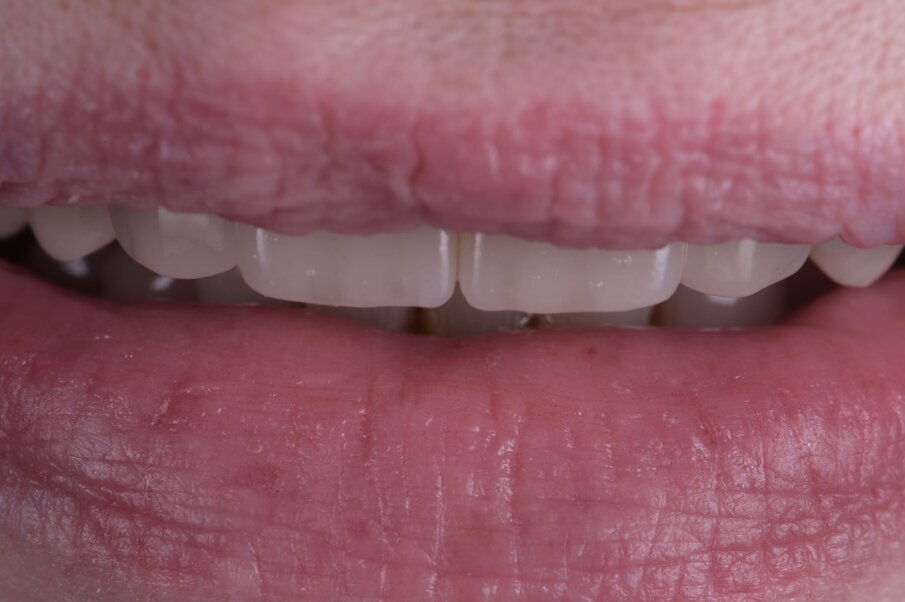

Fig. 48_Eseguendo fotografie laterali dx e sx riusciamo a vedere la naturale posizione del labbro superiore a riposo e nel sorriso, confrontandole (Fig. 3) riscontriamo il successo nella rimozione della flangia in resina con una rigenerazione ossea e con la forma coronale, rimuovendo il codice a barra presente in Figura 4.

Fig. 49_A maggior ingrandimento notiamo la naturalezza delle labbra giustamente umettate segno di una fisiologia ritrovata.